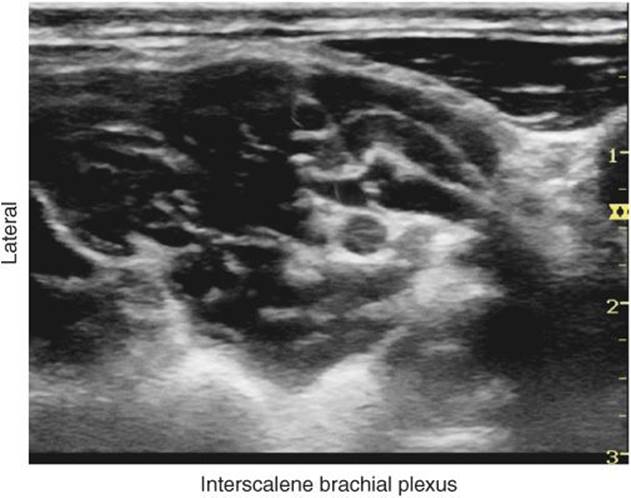

FIGURE 29-3. Interscalene brachial plexus is seen between middle scalene muscle and anterior scalene muscle. Carotid artery is seen medial at 1 cm depth in this image.

FIGURE 29-4. Typical image of the brachial plexus (BP). The BP is seen positioned between the anterior scalene muscle (ASM) and the middle scalene muscle (MSM). The superficial cervical plexus (white arrowhead) can be seen posterior to the SCM and underneath the prevertebral fascia. In this particular image, the vertebral artery (VA), carotid artery (CA), as well as the transverse process of C6 are also seen.